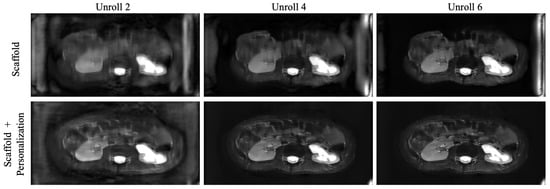

Figure 8 displays the output of the network D ( · ; Θ k ) after every two unrolls in the reconstruction, for an unseen site, immediately after federated training (Scaffold), as well as after fine-tuning (Scaffold + personalization). Artifacts are amplified in the baseline model, and personalization helps reduce their intensity.

Figure 8. Images across unrolls (output of D ( · ; Θ k ) ) for: (Top) Scaffold initialized model, and (Bottom) Scaffold + personalization model applied to an unseen client distribution.